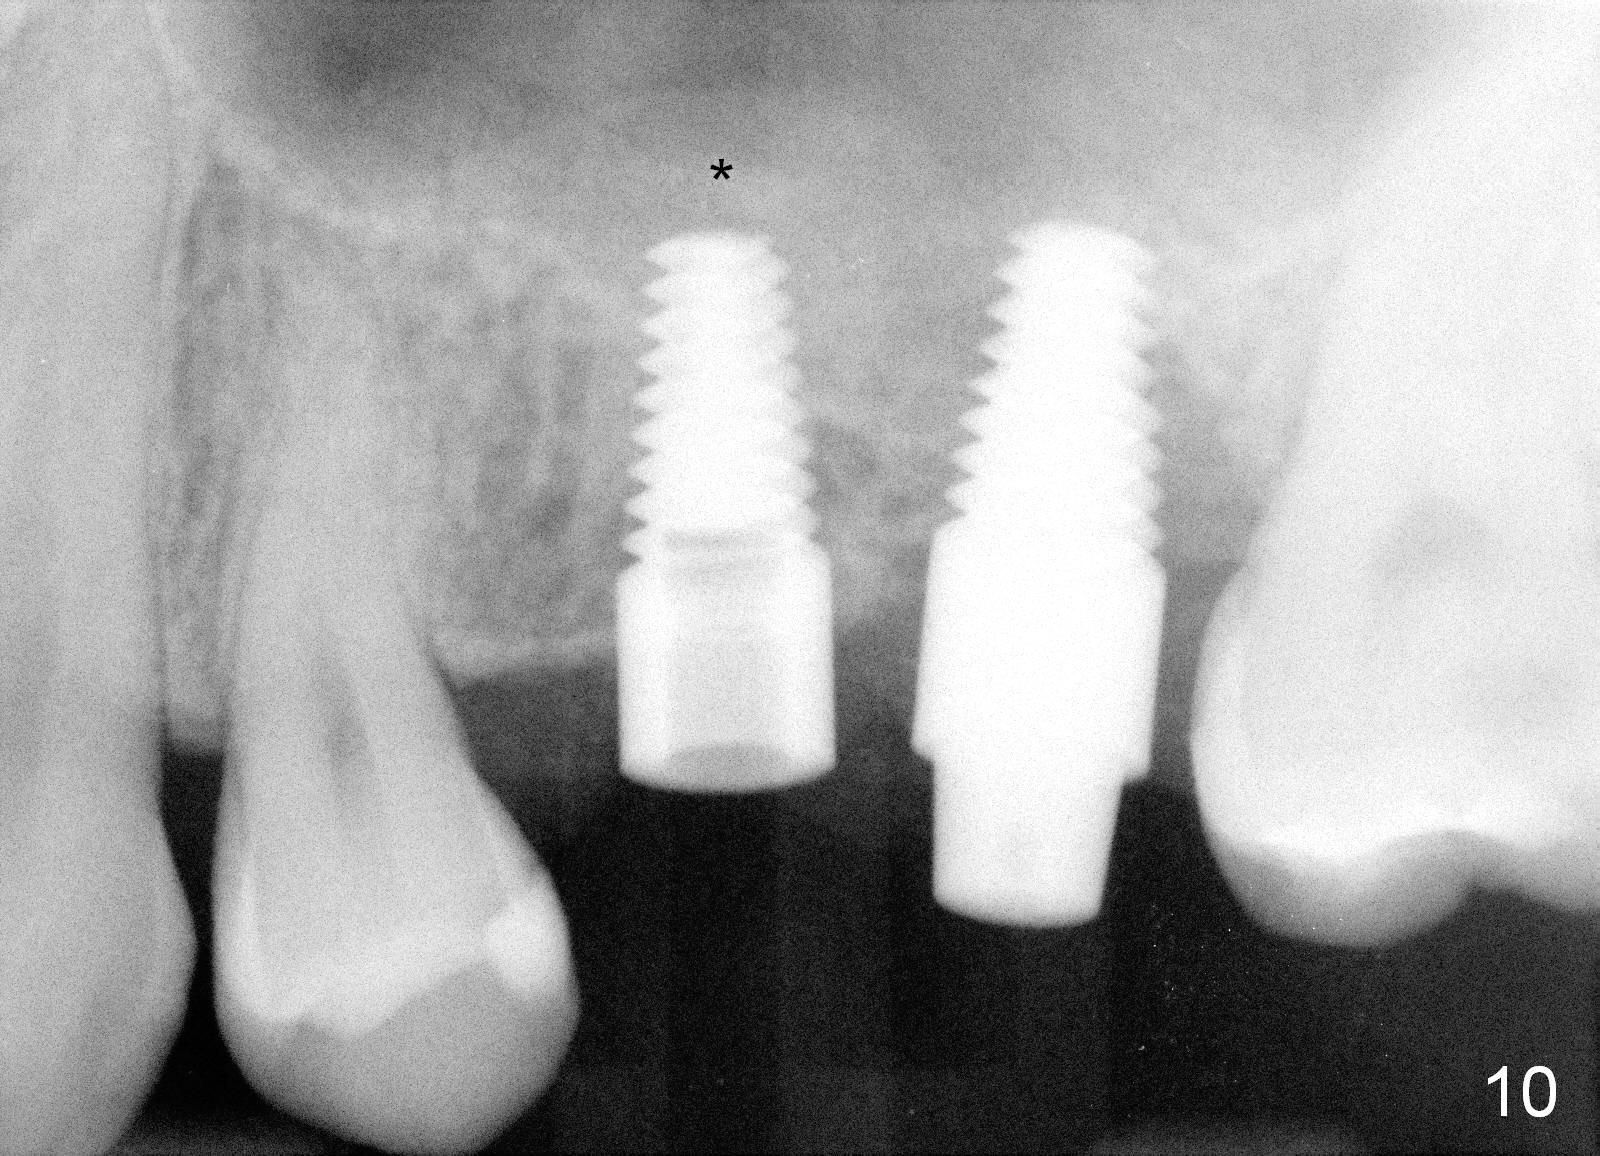

The patient returns for #13,14 implant placement. The ridge appears to be wide buccolingually (Fig.1 mirror view). A 4 mm tissue punch is used for access at the sites of #13 and 14. Osteotomy is initiated by using 3 mm trephine bur at the depth of 4 mm at both sites; 2 mm pilot drill is used to continue osteotomy at 8 mm deep at the site of #13. Sinus lift is accomplished by using tapered osteotomes 2,3 mm 6 mm deep, followed by 4.5x11 mm tap (Fig.2 T); 2 mm pilot drill (P) is reinserted into #13 osteotomy site with inadvertently penetrating the sinus floor. When the tap is removed from the site of #14, the sinus membrane is also found to be perforated. The sinus membrane at both sites is repaired by insertion of collagen dressing before bone graft. A 4x11 mm one-piece implant is placed at the site of #13 slowly hoping that it does not re-perforate the sinus membrane (Fig.3 O). Due to limited restorative height, the abutment portion of the one-piece is expected to be trimmed (Fig.4 O). In case of implant complication or failure, the implant may be difficult to be removed. Therefore the implant at the site of #14 is two piece one (Fig.4,5 I/A, 5x11 and 4x3 mm, respectively). The insertion torques for #13 and 14 are 35/40 and >60 Ncm. Immediate provisionals are canceled mainly because of patient's inability to open wide for long. Perio dressing is placed instead after adjustment of the height of the abutments. The patient experiences one episode of light nasal hemorrhage a few hours postop. Although the patient takes Amoxicillin for 1 week periop, the implant at the site of #13 dislodges 1 months postop (Fig.5). Immediate re-placement with a larger 2 piece one is canceled because of mild infection mesiobuccal to the implant at the site of #14 (Fig.6 >). Exploration around the latter implant reveals possible thread exposure in a small area. After copious irrigation with normal saline, Arestin is placed. Two months post exfoliation, the site is re-entered (Fig.7,8). There is a lingual defect. Osteotomy is initiated as buccal as possible. A 4.5x11 mm tapered tap penetrates the sinus floor without tearing the membrane (Fig.9). The same-sized implant is placed (25/30 Ncm) with sinus lift (Fig.10 *). The lingual defect is bone grafted. There is dehiscence lingually 7 days postop (Fig.11). Impression for final restoration is taken 1.5 months postop because of pending wedding. The crown has been in function for 2.5 months.

It appears that there is no problem for the pointed end of 1 piece implant to stick to the sinus. A critical step is to place the implant inside the alveolus with primary stability. Tissue punch does not provide good surgical exposure to the ridge.